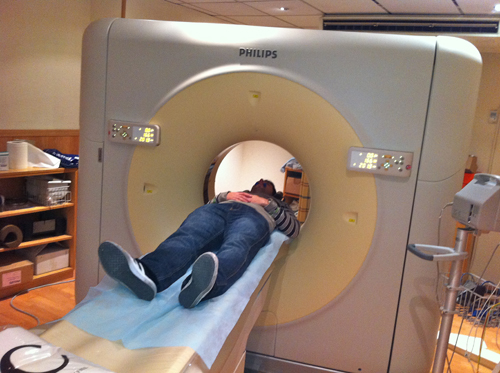

Palabras Clave: ELG: Estereolitográfico OH: Oclusión Habitual ORC: Oclusión en Relación Céntrica Paciente de 35 años de edad ,sexo masculino que lo derivan para implantar el tercer cuadrante. A la auscultación presenta ruidos articulares de tipo chasquido que remiten temporalmente luego de limitación de apertura bucal y maniobras quinesiológicas distractoras. También se observan recidivas de caries en algunos empastes y falta de disclusión canina de ambos lados. Se estudia el caso desde un punto de vista clínico, scanografico mediante Dentascan y tridimensional mediante montaje en articulador. A partir del scanner se obtienen datos para confeccionar modelo estereolitográfico (ELG),operar en el y construir férula quirúrgica dento-muco soportada. Habitualmente se procede directamente a implantar, dado que ese era el requerimiento del profesional derivante y el deseo del enfermo. Sin embargo, esa actitud enmascararía otro tipo de problemas que la boca presenta. Se consulta al odontólogo derivante, y coincide con mi opinión acerca de que si solo se lo implanta, sin corregir la posición mandibular, la situación de las ATMs, los empastes sin anatomía y la falta de disclusiones, el resultado final no será el deseado y su eficacia masticatoria no funcionará optimamente. Consultado el paciente coincide y acepta ese concepto y entonces procedemos a confeccionar un Jig de Lucia a partir del montaje de estudio, y lo dejamos puesto en boca toda la noche anterior a la consulta, para proceder a realizar un ajuste oclusal al día siguiente sin engramas anteriores, lo que facilita no tener que relajar nuevamente con laminillas de Long. En esta etapa pierde el implante correspondiente a la pieza 4.7 que traía en boca. Estabilizado el sistema, procedemos a la parte quirúrgica, comenzando por instalar la férula, retirar opérculos gingivales mediante bisturí circular, fresado óseo e instalación de implantes ,toma de impresión a cubeta fenestrada (pegando con metacrilato sin cambios dimensionales, los transfers a la cubeta especialmente diseñada.(1º método de pasividad protética utilizado), e instalación de tornillos de cicatrización. Inmediatamente de retirada la cubeta de boca y colocadas las réplicas de los implantes, procedemos a ferulizar los “ápices” de las réplicas para que no sufran movimientos durante el llenado de la impresión.(2º método de pasividad protética utilizado). Controlamos radiograficamente Tres meses después, procedemos a tomar nuevos registros de arco facial, registros intermaxilares en Oclusión en Relación céntrica, montaje de los modelos obtenidos intra operatoriamente y confección de un conjunto de cuatro coronas provisionales de metacrilato en el sector implantado y las correspondientes al maxilar superior. Verificada la perfecta función de todos los componentes, ausencia de todo tipo de síntoma y comprobada la paz en todo el sistema, procedemos tiempo después a confeccionar las fundas definitivas, que constituyen el “cerrojo” de la dinámica del mismo. Por último, corroboramos la oclusión fundamentalmente en lo que hace a la: